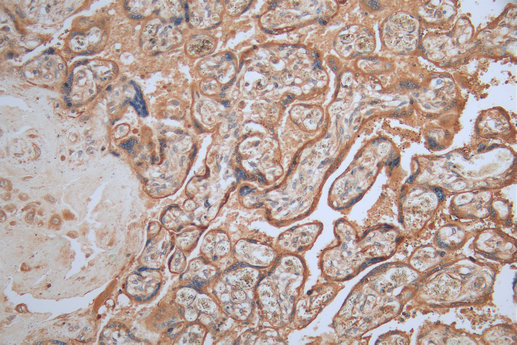

COL4A2基因是編碼 Type IV Collagen Alpha 2 鏈的基因,屬于膠原蛋白家族成員。該蛋白參與血管形成、結構維護和細胞上皮基底膜的

COL4A2基因突變是一種常見的遺傳變異,能夠導致多種疾病的發生。COL4A2基因編碼的是膠原 IV α2鏈,在體內主要參與形成基底膜,